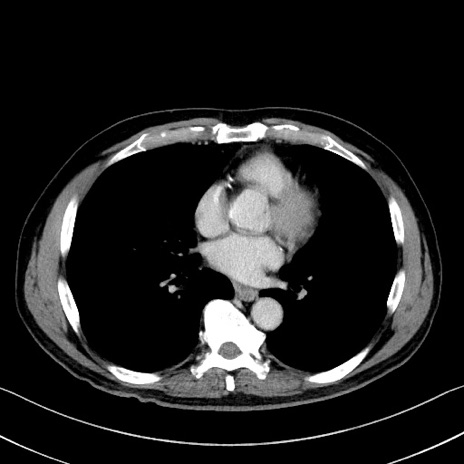

冠状断像